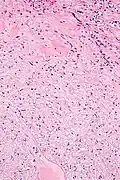

| Micrograph of a renal medullary fibroma (bottom of image). Renal tubules are seen at the top of the image. H&E stain. | |

They consist of bland spindle-shaped or stellate-shaped cells in a loose stroma. Renal tubules may be entrapped.

Low mag. -